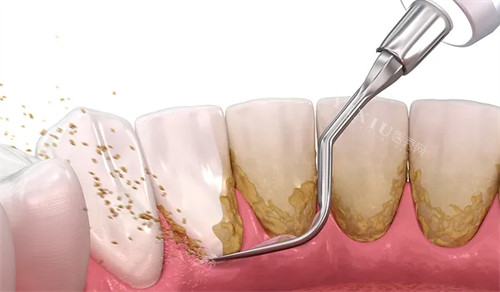

洗牙正式开始,一开始,我心里特别忐忑,担心会很疼。医生操作很轻柔,先拿着一个小器械在我牙齿表面轻轻刮擦,能明显感觉到牙结石被一点点清理下来,伴随着 “嗡嗡” 的声音,还有一股酸酸胀胀的感觉,但完全在可承受范围内。清洗到后槽牙的时候,因为牙结石比较多,稍微有点刺痛,我下意识动了一下,医生马上停下来问我是不是不舒服,调整了力度后才继续。整个洗牙过程中,医生还时不时停下来让我漱漱口,冲掉嘴里的碎屑,特别贴心。